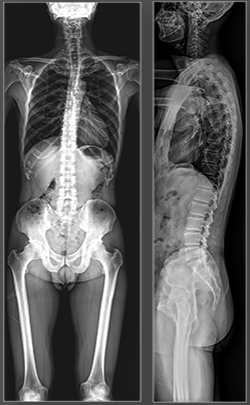

SLOT Advance, available on the Sonialvision G4 system, provides long leg and spine images.

Slot images are acquired using a narrow perpendicular X-ray beam tracking past the patient, producing a long image with almost no geometric distortion or magnification and very accurate measurements.

In Slot Advance, due to the perpendicular nature of the X-ray beam, there is practically no geometric distortion or elongation of the acquired image.

As such, the resultant Slot Advance images are very accurate in their anatomic representation.

- • Cobb Angle measurement.

Using Tomosynthesis images for measuring total spine alignment

Measuring total spine alignment on the Sonialvision system using a combination of Slot and Tomosynthesis imaging. Read more......